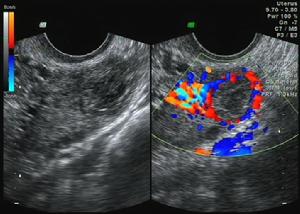

血管型平滑肌瘤(4)血管型平滑肌瘤(vascular leiomyoma):巨检肿瘤像普通肌瘤,切面色较红。镜下见血管性平滑肌瘤中血管很丰富,血管内皮细胞很明显,瘤细胞围绕血管排列,与血管平滑肌紧密相连,可见血管壁的平滑肌细胞与肌瘤细胞之间有移行过渡。核分裂象极少(图5)。 医学百科网 | YxBaike.Com

(6)静脉内平滑肌瘤病(intravenous leiomyonmtosis):极罕见,是一种由子宫肌瘤向脉管内生长或由脉管壁本身的平滑肌组织增生后突向管腔内的肿瘤,除静脉外淋巴管也可受累,所以又称脉管内平滑肌瘤病(intravascular leiomyomatosis)。静脉内平滑肌瘤病可以超出子宫,若未完全取净,可以在静脉内沿静脉延伸达下腔静脉,甚至到心脏(极少)。叶永清等(1996)报道1例子宫颈残端及下腔静脉平滑肌瘤,瘤栓延伸至右心房及右心室。由血管外科、心脏外科和妇科联合手术,成功地将下腔静脉及宫颈残端平滑肌瘤取出,术后2年随访患者健康。组织学是良性平滑肌瘤。绝大多数患者同时有子宫肌瘤或过去有子宫肌瘤手术史。临床症状无何特殊,可有月经过多或腹部肿块,检查子宫增大,一般术前不易诊断。彩超显示肌瘤有多个结节且瘤体内血供丰富,此为子宫脉管内平滑肌瘤的声像特点,对术前诊断很有价值。手术时如见到子宫表面有一种特殊的静脉形态或暗红色结节,或阔韧带内有结节或暗紫色包块,或膀胱腹膜反折处静脉、宫旁静脉、卵巢静脉增粗并触之变硬,则应提高警惕。病变主要在子宫肌壁或盆腔静脉内,子宫肌壁剖面内可见到多个灰白色大小不等的结节0.1~2cm,四周有明显的腔隙,此腔隙即为扩大的脉管,将腔隙内肿瘤分离可见有蒂与管壁相连,肿瘤呈蠕虫样,条索状和分支状,取出后留下圆形腔隙内壁光滑;也可在肌间肌瘤边缘或黏膜下肌瘤蒂根附着处有扩张的脉管,肌瘤似栓子样突入脉管内。子宫外盆腔静脉内平滑肌瘤可在阔韧带见到结节,宫旁或卵巢静脉内有条索状肿块,静脉切断后可将肿瘤从静脉腔内拉出来,有时静脉腔被充满,继续增大可成为圆形,外观灰白色或紫褐色,质地可以从软、海绵状到橡皮样或硬。镜下肿瘤由形态学良性的平滑肌瘤所组成,长在衬有内皮细胞的脉管中,大多数为静脉少数为淋巴管,表面为扁平内皮细胞所覆盖,肿瘤内有厚壁的小血管,可见透明变性,细胞形态正常,无核分裂象或仅有少量分裂象,肿瘤可以游离存在于管腔内也可以与管壁相连。镜检时应注意核分裂象以鉴别良恶,核分裂象<2个/10HPF为脉管内平滑肌瘤;2~5个/10HPF为脉管内平滑肌瘤具潜在恶性;>5个/10HPF为平滑肌肉瘤侵入脉管内。静脉内平滑肌瘤病治疗后易复发,于子宫切除术时病变未超出子宫或将子宫外病变已完全切净,日后还可以在其他脉管内发生。有时是在子宫切除若干年后发生。复发与保留卵巢的内源性雌激素有关,主张作全子宫、双附件及子宫外肿瘤切除,可减少复发,改善预后。